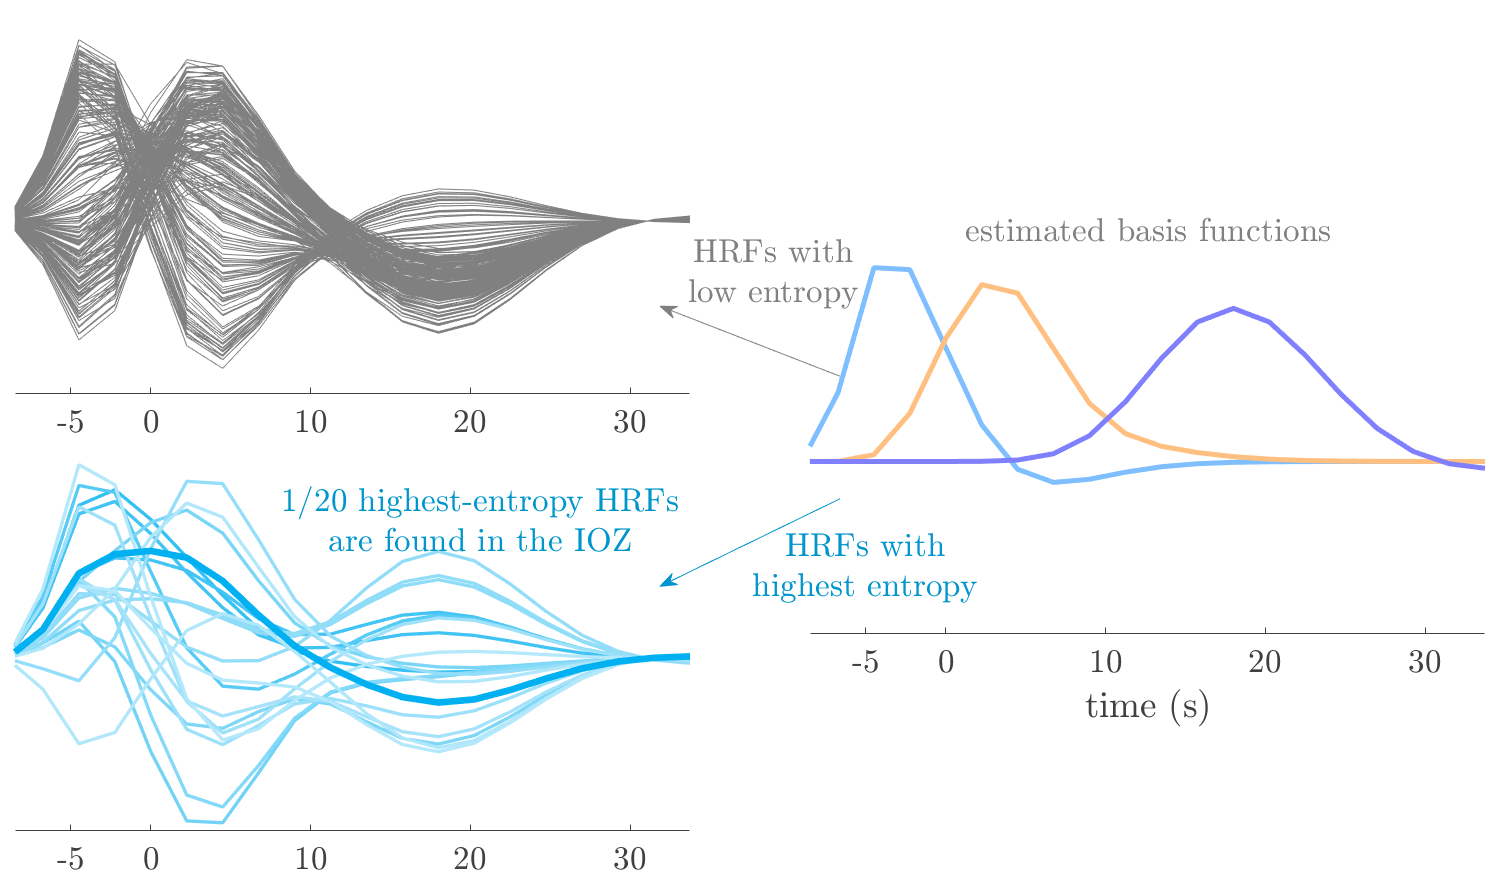

We analyze the solution with sources. Figure 1 shows the EEG signatures and HRF waveforms. One of the sources is highly correlated to the MWF reference (in grey), which was already known from Table B.3. This IED-related source had a typical low-frequency spectrum, which is expected for the typical spike-and-wave interictal discharges. The topography is relatively diffuse, although the highest amplitudes are mostly in the left hemisphere. This is in accordance with the lateralization of ictal onset zone (left temporal lobe, cfr. Table 1). There are some noteworthy observations to be made about some of the other components. The fourth has an unusually sharp spectrum, is mainly localized on two nonadjacent center electrodes, and is sustained for a single period of many seconds Hence, this component likely captured an artifact (of yet unknown origin), although we spotted no large-amplitude changes in the EEG itself. Similarly, the third source is only present at one frontal electrode, and exists in a frequency range above 20 Hz. It might represent a muscle artifact, e.g., due to frowning or twitching of some muscles in the forehead. The HRFs of all ROIs are shown in Figure 1(b). Two of the basis functions seem to have converged to a very similar waveform, which is an unfortunate possibility if two initial HRFs are too close to the same local optimum in their respective parameters. This reduces the expressive power of the basis set, which is clearly visible, since many ROIs have a nearly identical HRF. One of the twenty ROIs with the highest-entropy HRF overlapped the IOZ, although clearly this HRF (bold line) is not among the most dissimilar waveforms for this patient. This is also visible in Figure 2: both the HRF entropy and extremity maps show a small overlap with the delineated IOZ. Despite the good correspondence in the EEG domain, no significant (de)activation of the IED-component is found inside the IOZ.

We analyze the solution with sources, and show the results in Figure 3 and 4. As for patient 1, we found a source which is strongly correlated to the MWF envelope, and which had a mostly low-frequency behavior characteristic for spikes. The topography is mostly uninformative, and does not clearly correspond to the patient’s clinical data. The third source is mostly present at both sides of the head, is very sparsely active in time, and has a high-frequency content: this is most likely an artifact due to the neck muscles. Again, there is one of the highest-entropy HRFs which belongs to a ROI in the IOZ. Now, the waveform is clearly resolved from the other HRFs, through the strong initial dip (before 0 seconds). Such a dip is sometimes observed in HRFs, but its underlying physiological mechanism is not yet fully understood. It is possible that this dip reflects altered vascular autoregulation near the IOZ (cfr. the explanation in the Section 1 of the main text), or a rapid depletion in oxygen due to IED generation (before the IED becomes visible on the EEG). Figure 4 furthermore shows that the IED-related component is significantly active in parts of the IOZ, and deactive in others. As mentioned earlier, this deactivation may or may not be due to errors in sign correction. Interestingly, the ROI with the high alteration in neurovascular coupling is distinct from both the activated and deactivated ROIs.

We analyzed the solution with sources, and show the results in Figure 5 and 6. There is one source which is mostly correlated to the reference (but not extremely, see also Table B.3). This source had a right-temporal focus, conform the diagnosis in Table 1. The second source illustrates the phenomenon of an erroneous sign exchange between the spatial and spectral profiles. Also one of the HRFs has a negative polarity, which is a failure of the sign correction procedure (in this case, because there is exceptionally no positive overshoot). However, the HRF variability metrics are still interpretable, and indeed two ROIs among the ones with the highest-entropy HRFs overlap with the IOZ. The IED component is significantly active in a tiny portion of the IOZ (cfr. Figure 6). The second source is significantly active in symmetrical parts of the parietal lobe. Given its ongoing fluctuation over time, we hypothesize that this source captures a resting state network (RSN).

We analyze the solution with sources, and show the results in Figure 7 and 8. There is a clear IED-related component, with a very high correlation to the MWF reference, a typical spectrum, and an anterior-temporal focus, which corresponds very well to the patient’s diagnosis (cfr. Table 1). The fifth source seems present at only one channel, and has spectral harmonic at Hz and Hz. One of these peaks is reminiscent of the fourth component in patient 1. As Figure 8 shows, the HRF entropy and extremity prove to be strong biomarkers for the IOZ in this case, and also the significant IED activation and deactivation allow correct localization. In Figure 7, it is clear that some HRFs may still have the wrong sign, which means that the interpretation of ‘active’ and ‘deactivated’ is flipped in those ROIs. Hence, regions of significant deactivation are in fact significantly activated. The fourth source had a significant overlap with the auditory RSN, and its spectrum reveals activity in the band.

We analyze the solution with sources, and show the results in Figure 9 and 10. One source is strongly correlated to the MWF, while the other source is likely an artifact, given its very sparse temporal profile. Both sources coincide at one high-amplitude peak, by which we infer that this is probably an artifactual period in the signal. Indeed, when inspecting the original EEG signals, we found high-frequency muscle artifacts at these times. This source also had no significant activation in its spatial map, which corroborates its non-neuronal origin. The IED-related source had a broader spectrum than most other cases, and an uninformative topography. None of the ROIs with high-entropy HRFs is located in the IOZ. The pseudo t-map provides correct localization of the IOZ, however.

We analyze the solution with sources, and show the results in Figure 11 and 12. We found a clear IED-related component, with a characteristic spectrum and a topography which is backed up by the patient’s diagnosis (left anterior-temporal IOZ). The fourth source has a very similar topography and spectrum to the fifth source in patient 5. One HRF inside the IOZ had a high-entropy, and is distinguishable from the others by its very sluggish waveform, i.e., it is smeared out in time, with no sharp over- or undershoot. Also the pseudo t-map provided an accurate localization of the IOZ. Notably, in this patient, the extremity metric misses the deviating HRF in the IOZ (while the entropy metric picks it up). The second source overlapped with the frontal part of the default mode network (DMN), and is active in the and low bands.

We analyze the solution with sources, and show the results in Figure 13 and 14. We found two components which had correlated time courses. At the time of the peaks, we found higher-amplitude events in the EEG with dubious origin, hence they may or may not be artifacts. One of both components is more strongly correlated to the MWF, and its activation is concordant with the IOZ. The second component shows high overlap with the sensorimotor network. For this patient, none of the IOZ’s ROIs had extreme values of either HRF metric.

We analyze the solution with sources, and show the results in Figure 15 and 16. In this patient, there is only a moderate correlation of a component with the MWF reference time course. This component’s topography (left occipital) agrees with the clinical description, however. The HRF extremity (and not the entropy) is high in a small part of the IOZ. Both the significant IED activation and deactivation allow correct localization as well. The second source seemingly captured high-frequency oscillatory activity in the sensorimotor network, similar to the previous patient.

We analyze the solution with sources, and show the results in Figure 17 and 18. The IED-related source had a high correlation with the MWF reference, but an odd bimodal spectrum. Its EEG topography is very consistent with the clinical description. Both HRF extremity and entropy are useful biomarkers for the IOZ. The IED activation and deactivation maps each had a very small overlap with the IOZ. The second source is temporally sparse and captures high-frequency EEG variations, which we identified as muscle artifacts.

We analyze the solution with sources, and show the results in Figure 19 and 20. Again we observe an IED-related source and a seemingly artifactual source with a spectral peak near 34 Hz. Many of the high-entropy HRFs are highly noncausal, and are associated to ROIs inside the IOZ. Hence, with both HRF metrics, the highest-scoring ROIs provides good localization of the HRF. While there are no significantly active ROIs in the IOZ, there are several significantly deactivated ROIs, which may indicate that the sign standardization was not done flawlessly (cfr. also some of the negative-peaking HRFs for patient 10). Surprisingly, the second source had one significantly active ROI, which overlaps with the IOZ, but which did not match its EEG topography. Hence, the nature of this source remains ambiguous.